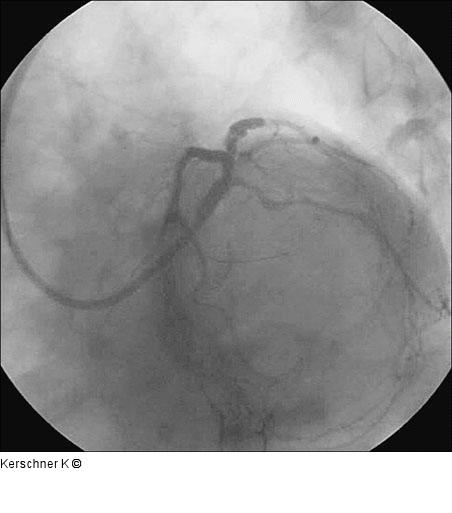

Abbildung 9: Ergebnis nach Crush Ergebnis nach Crush - LAO / kaudal |

Abbildung 9: Ergebnis nach Crush

Ergebnis nach Crush - LAO / kaudal |